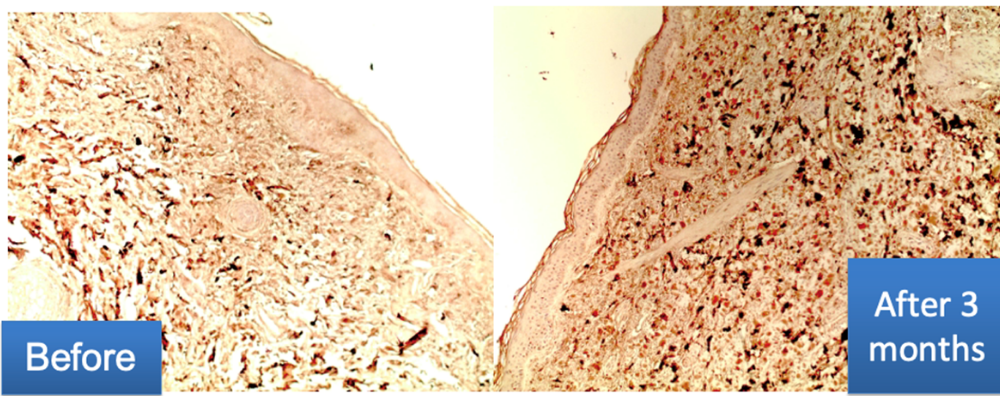

Immunhistochemische Untersuchung:

- Der Gehalt an Kollagen III in der Dermis ist deutlich erhöht.

- Die Bildung von längsgerichteten Fasern